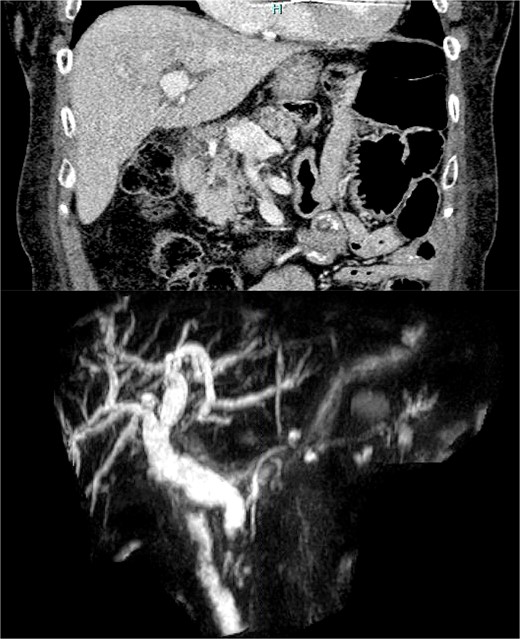

This patient was a 77-year-old female with a past surgical history including open RNYGB and open cholecystectomy. She initially presented with abdominal pain and transaminitis, although her total bilirubin was normal. A CT scan revealed intrahepatic and extrahepatic bile duct dilation with a cystic lesion within the pancreatic head (Fig. 1a). Magnetic resonance cholangiopancreatography (MRCP) confirmed a high-grade stricture of the distal common bile duct (CBD), concerning for malignancy (Fig. 1b).

(a) CT scan image of the cystic lesion within the head of the pancreas. (b) MRCP image of intrahepatic and extrahepatic bile duct dilation with abrupt change in caliber at the distal CBD.